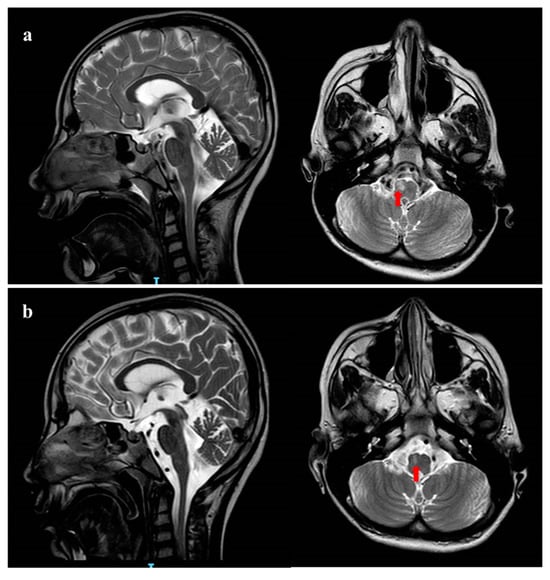

2.1. Clinical Characteristics